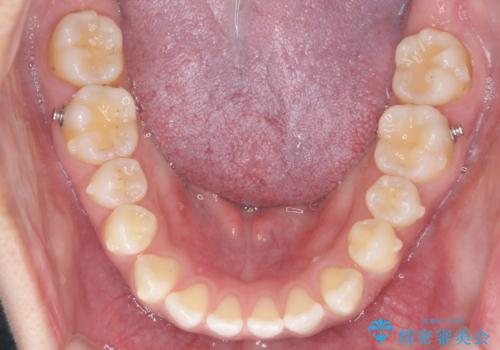

受け口、すきっ歯を インビザラインで モニター治療

- 前歯のすき間と受け口を気にして来院。

マウスピースでしっかり閉じています。

下の前歯を後方に移動するため、ゴムを上下のマウスピースにかけてもらいました。